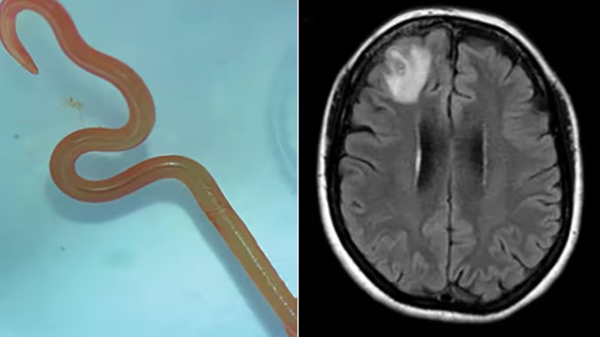

Read Moreفي حادثة طبية مدهشة، اكتشف أطباء في مستشفى كانبيرا في أستراليا دودة حية في دماغ امرأة تبلغ من العمر 64 عاماً.وتمكنت الدكتورة هاري بريا باندي جراحة الأعصاب من سحب الدودة التي يبلغ طولها 8 سنتيمترات من المريضة. وفق ما أفادت صحيفة “الغارديان”. تشوهات في الدماغوأدخلت المريضة، مستشفى محلي في نيوز ساوث وليز في أواخر يناير